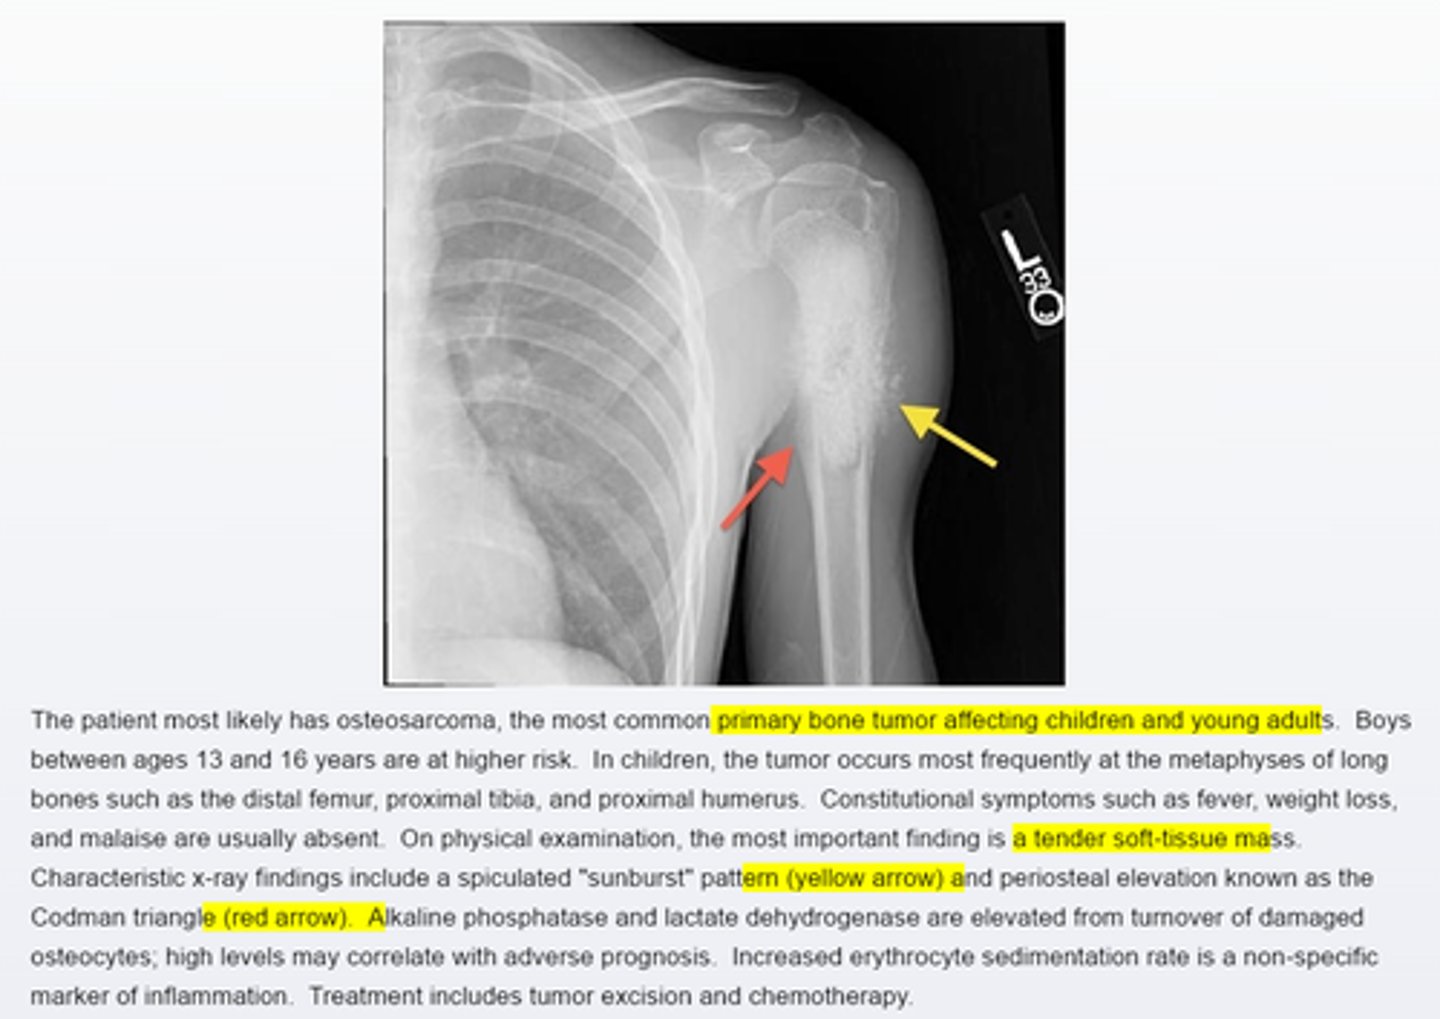

Osteosarcoma